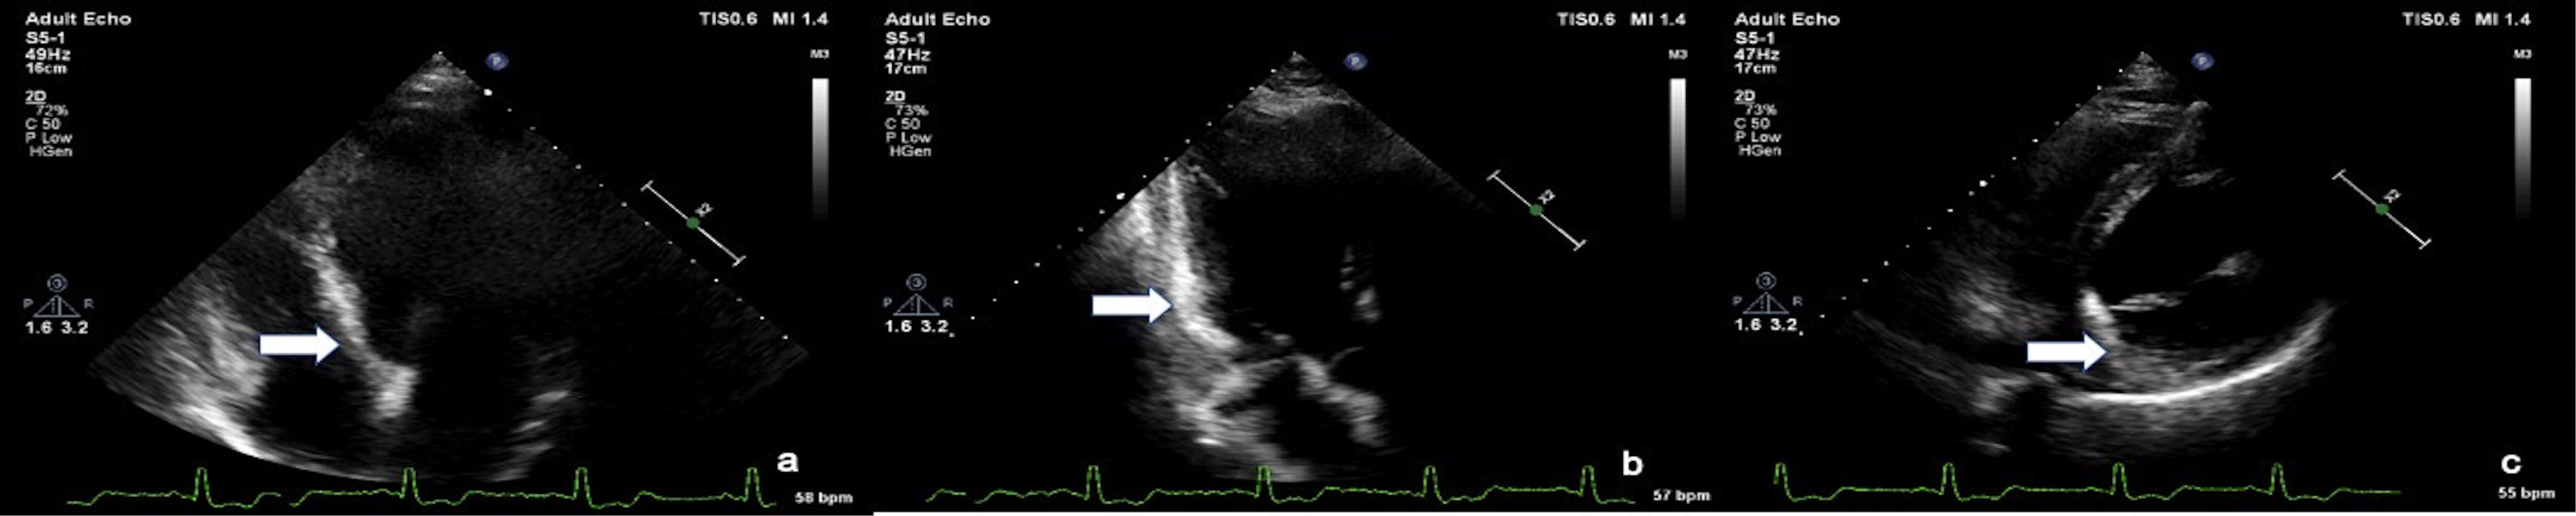

The patient had no history of hypertension, diabetes, smoking, or dyslipidemia. He denied any history of angina or syncope. On examination, the patient was having tachycardia and a blood pressure of 80/50 mm Hg with diaphoresis. During the episode of tachycardia ECG revealed monomorphic VT (right bundle branch block morphology with superior axis) (as shown in ). Sinus rhythm was immediately achieved by direct current cardioversion. Electrocardiogram (ECG) during sinus rhythm showed q waves in inferior leads with T inversion and QTc interval of 420 ms (as shown in ) suggestive of evolved inferior wall MI. Blood investigations including complete blood count, electrolytes including potassium, calcium magnesium, liver and renal function tests, and the lipid profile were within normal limits. Troponin T was elevated at 4.3 ng/mL. CD4 cell count of the patient was 987/mm3. Echocardiography of the patient showed hypokinesis in right coronary artery (RCA) territory with an EF of 50 % (as shown in , Supplementry File 1, Video S1). He was treated with amiodarone infusion, dual antiplatelets (aspirin and clopidogrel), atorvastatin, metoprolol and low molecular weight heparin. The patient underwent coronary angiography which revealed spontaneous coronary artery dissection in mid RCA (as shown in , Supplementry File 2, Video S2). Rest of the coronary vessels were normal (Supplementry File 3, Video S3). In view of lack of flow limiting stenosis and TIMI III flow, revascularization was not done. For secondary prevention, implantable cardiac defibrillator has been advised for the patient, but the patient has refused the same due to financial reasons. The patient developed no further episodes of VT during hospital admission and on follow up after a month.

jcvtr-14-71-g003

Figure 3. Echocardiogram images in a Apical 4 chamber view, b. Apical 3 chamber view, c. parasternal short axis view showing increased echogenicity of myocardium in the RCA territory (arrow)